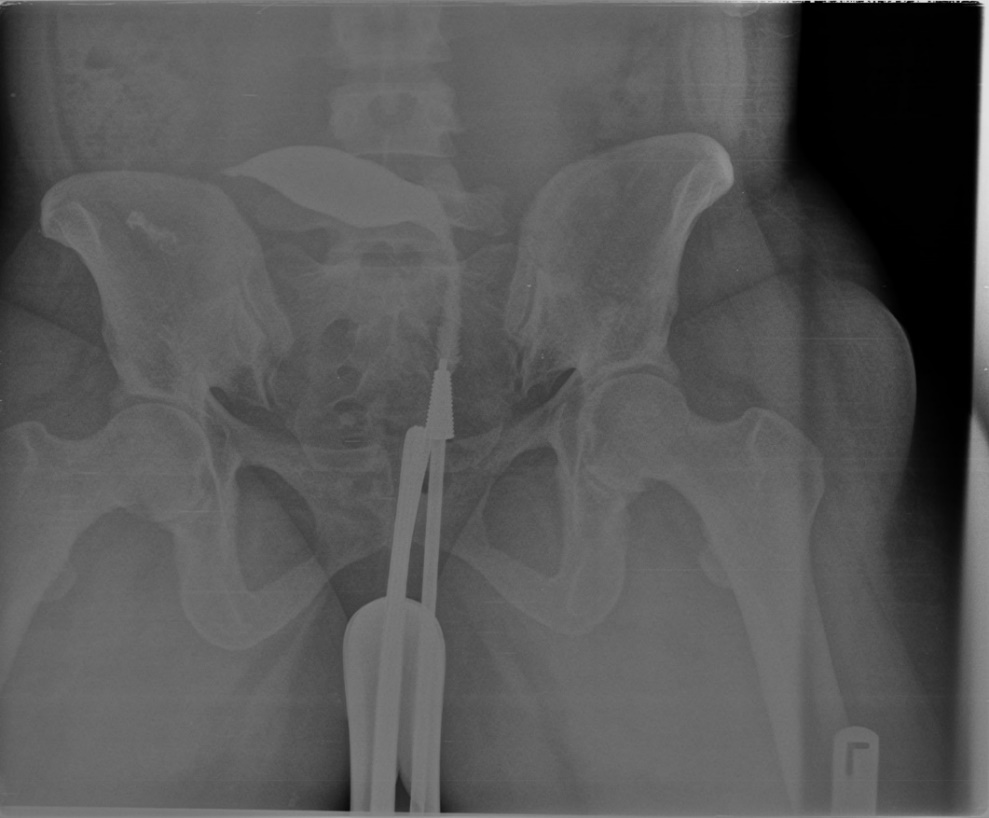

Figure 3: shows bilateral proximal tubal occlusion

The prevalence of tubal pathologies in this study was 29.7% with bilateral proximal tubal occlusion being the most common abnormality, accounting for 10% of cases. This finding corroborates studies conducted in Lagos20 and Oghara21, where similar patterns were reported. However, a study in Zaria22 found unilateral tubal occlusion to be more common. Among unilateral cases, right sided blockages (5.7%) were more prevalent than left sided (2.6%), consistent with findings in Sokoto15 and Lagos20. Conversely, studies in Maiduguri16 and Korle-Bu14 reported left sided predominance. Some cases of bilateral proximal tubal occlusion were presumably due to tubal spasm; in this study all patients had intramuscular injection of hyoscine bromide (Buscopan) at the beginning of the procedure which is thought to prevent spastic tubal occlusion.